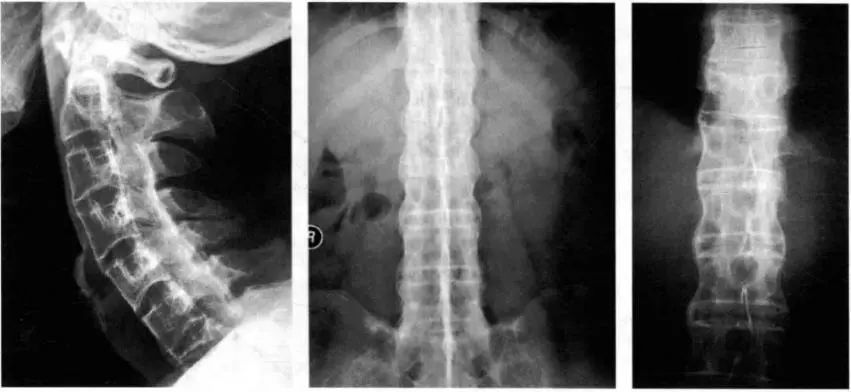

本文图片

CT平扫:双骶髂关节间隙变窄 , 关节面毛糙或骨性融合8